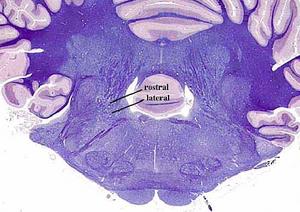

secciones transversales a diferentes niveles del tronco del encéfalo mostrando la localización de los núcleos neuronales aferentes de los nervios craneales

AFERENTES:

Somatoaferentes:

generales (GSA): boca y cara

-especiales (SSA): sentido de la visión y oído

Visceroaferentes:

- generales (GVA): recogen sensación de faringe y laringe

-especiales (SVA): sentido del gusto y del olfato

correspondencias entre la localización de los núcleos neuronales en diferentes cortes.